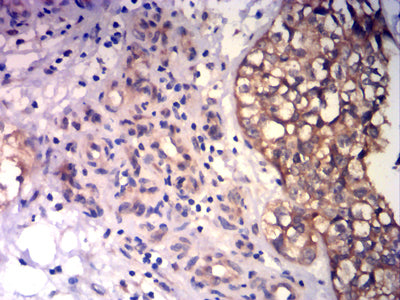

Immunohistochemical analysis of paraffin-embedded human bladder cancer tissues using CD43 mouse mAb with DAB staining.